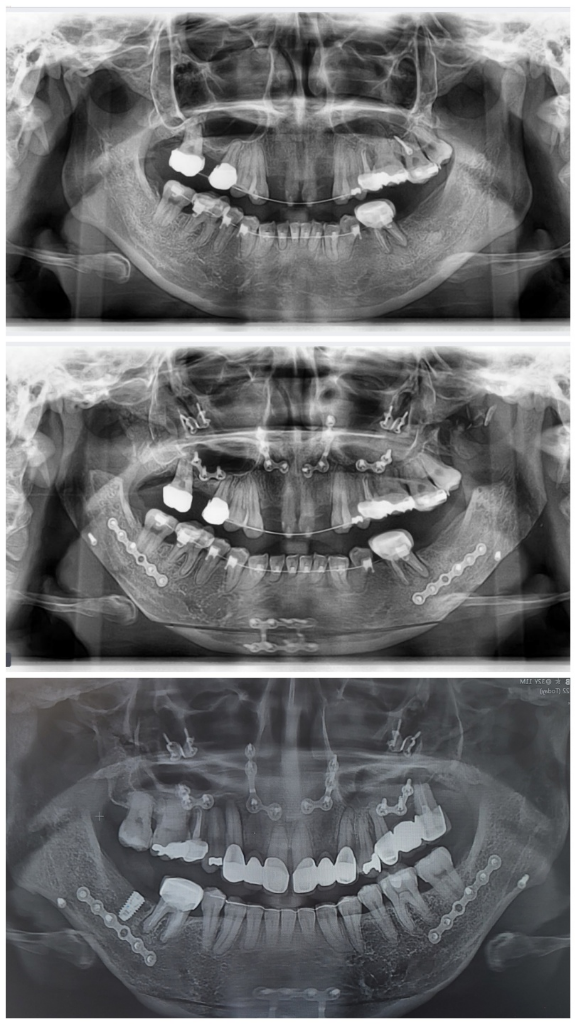

한쪽이 치아도 그렇고 뒤로 빠져있어요,

목구멍? 기도도 답답한 느낌이예요..

현재 상악 임플란트 수술 예정으로 발치후 뼈이식했어요

(핀제거도 다 했어요, 중심이 안맞는것, 교합 좀 봐주세요)

상악 치아 망가져서 부비동염오고 난리도 아니구ㅠㅠ

양악 케이스면 뼈이식해서 생착 기달려야해서 지금하거나 시기맞춰서